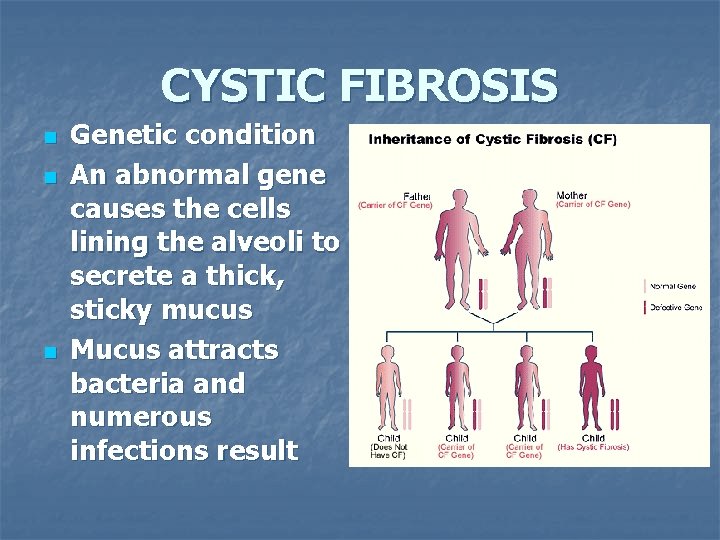

CYSTIC FIBROSIS n n n Genetic condition An abnormal gene causes the cells lining the alveoli to secrete a thick, sticky mucus Mucus attracts bacteria and numerous infections result